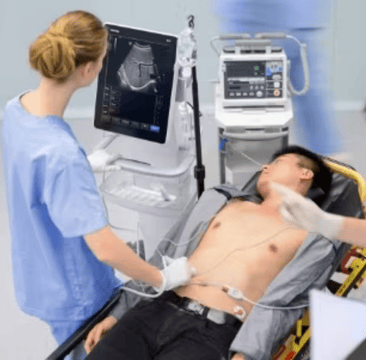

Point of care ultrasound?refers to the use of ultrasound at a patientŌĆÖs bedside for diagnostic or therapeutic purposes. A clinician uses?point of care ultrasound (POCUS)?to guide the evaluation and diagnosis in conjunction with a traditional medical examination.

A point of care ultrasound exam involves using ultrasound to answer specific clinical questions or guide a procedure at the ŌĆ£point of care,ŌĆØ whether in a hospital or a remote setting.?It provides a quick, non-invasive way to speed the diagnosis and treat the patient more effectively.

POCUS encompasses a bedside ultrasound but is usually performed by a physician and provides much more flexibility. While traditional?ultrasonography?certainly still has its place, POCUS allows the physician to review and interpret images and make critical decisions at the point of care.

POCUS can be used in virtually any care setting. However, because of its ease of use and speed of diagnosis, it has proven invaluable in Emergency Medicine. This technology can also combine with other assessment tools to assist with a quick diagnosis.?Below are a few examples of how POCUS can assist in emergencies.